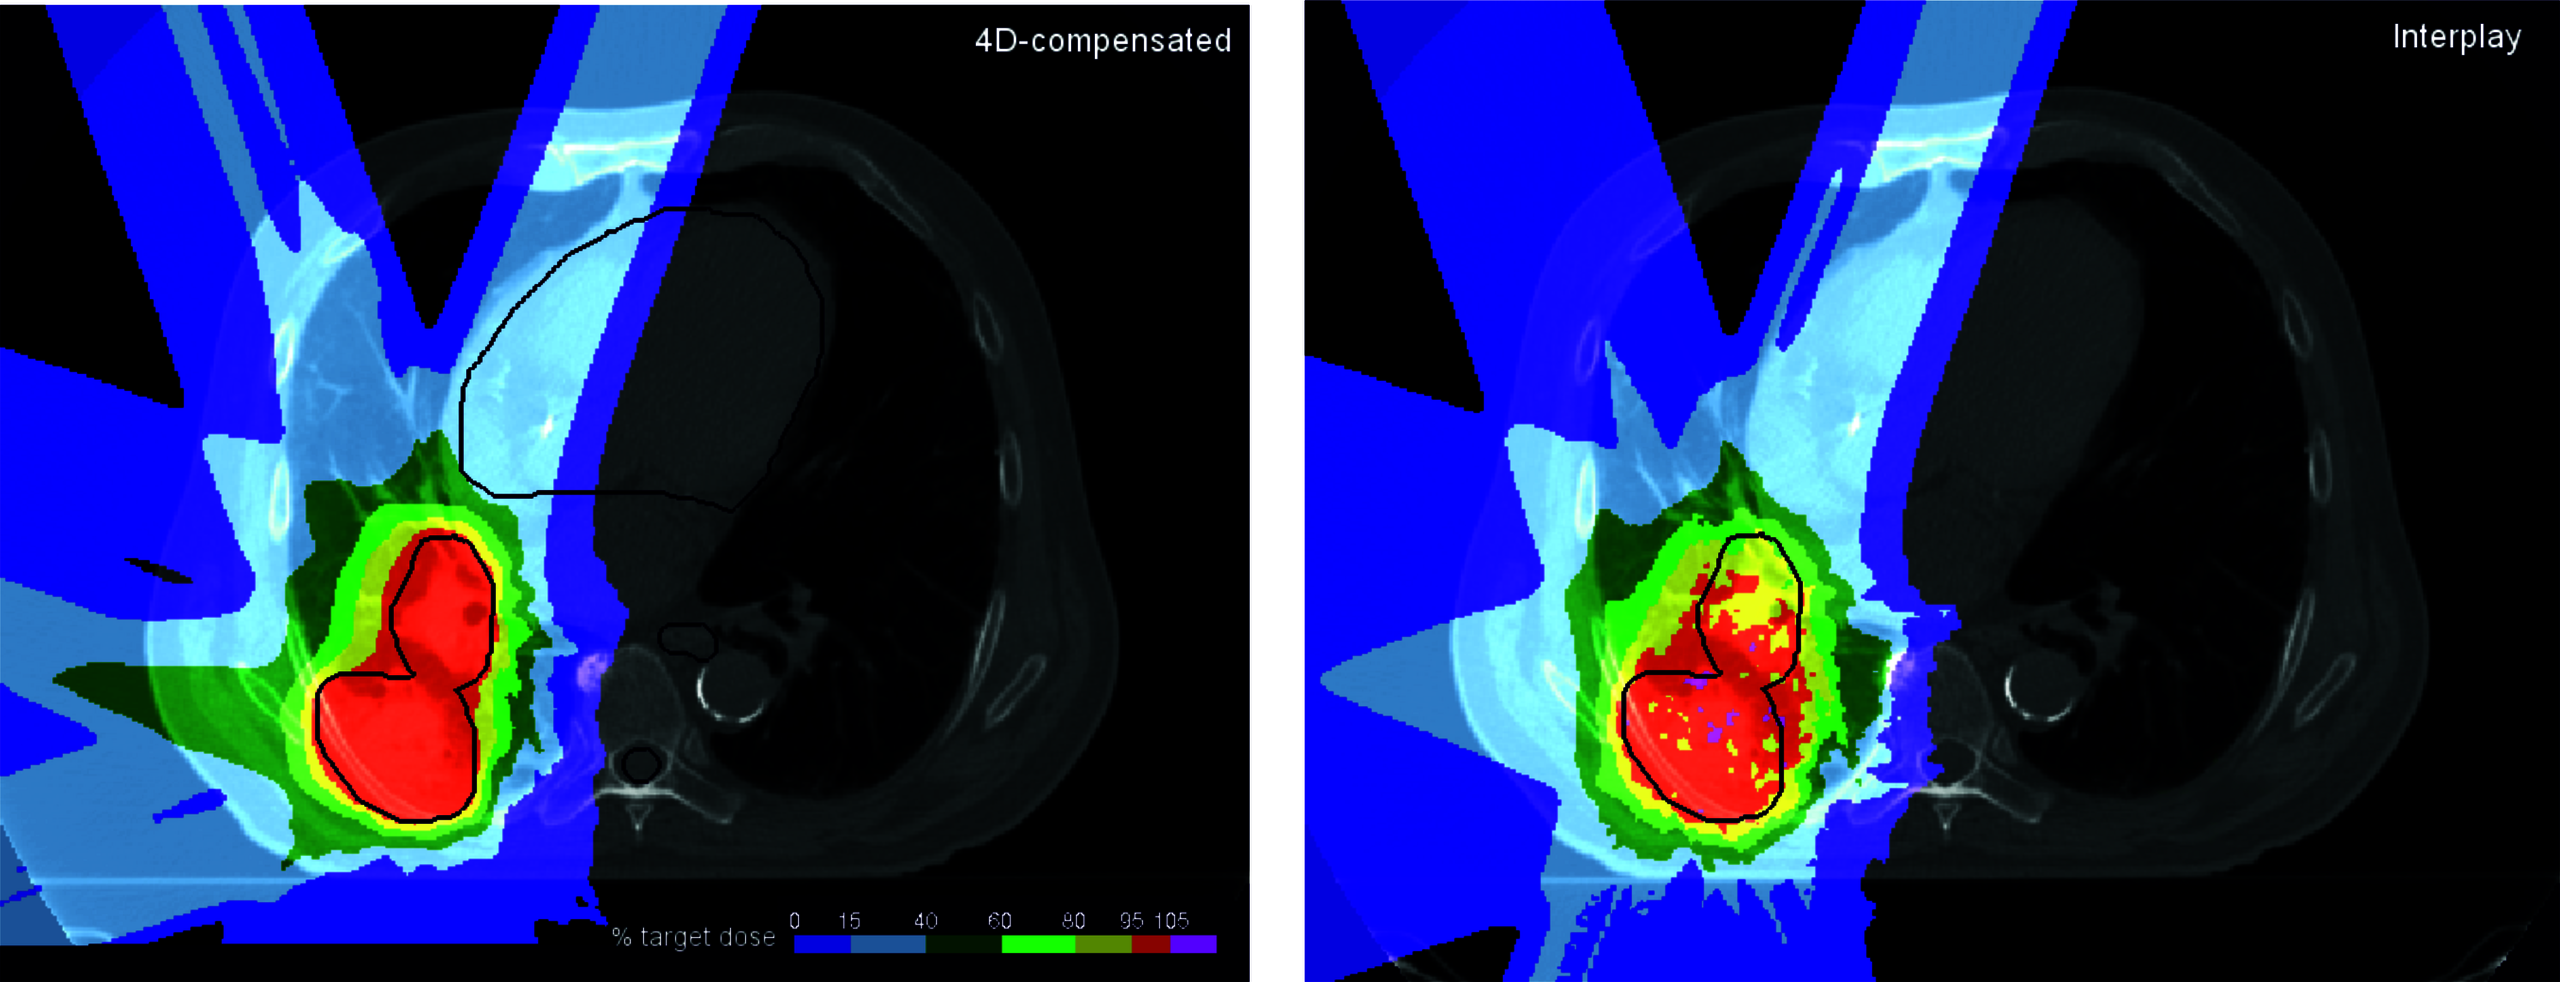

Compared to conventional photon radiotherapy, dose delivery to moving (4D) targets, such as lung, liver or kidney is more complex mainly due to two factors: (1) interference between target and beam motion (interplay) and (2) the changing range to the target due to its motion.

Interplay leads to highly variable over- and underdoses, which prevent the simple use of margin concepts for motion compensation as used in photon radiotherapy. The finite range of ion beams in matter is a major advantage, but also require precise knowledge of the radiological pathlength to the target tissue. As this pathlength changes with motion especially in the lung, dedicated mitigation strategies are necessary.

The Medical Physics group has developed and investigated efficient motion mitigation techniques including beam gating, rescanning, beam tracking, and 4D-optimization strategies. All techniques were implemented and experimentally validated at GSI’s Cave M with a number of in-house developed motion platforms and phantoms. The primary aim of these studies is to achieve conformal dose coverage with maximum sparing of healthy tissue.